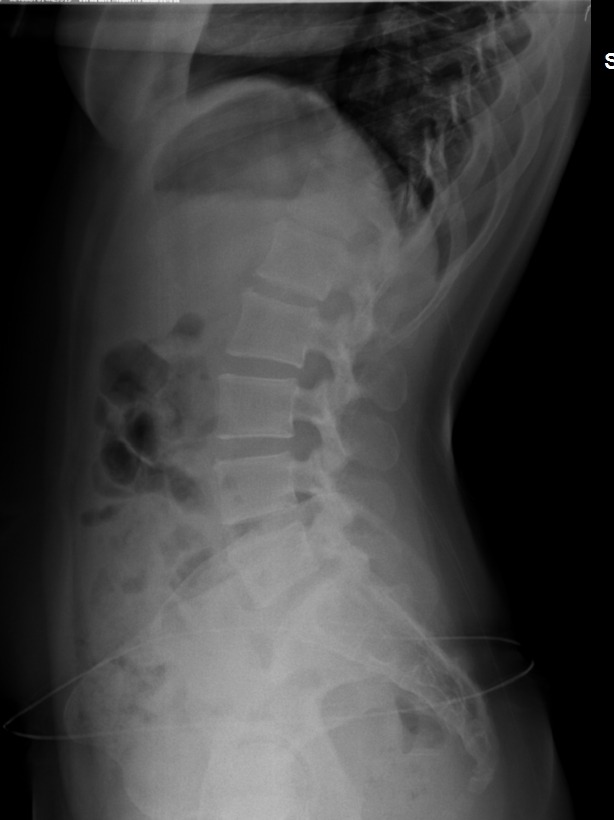

4. 요추 과전만, sacral angle증가

5. 경추 reverse curve

- 거의 모든 측만증에서 경추는 일자목 or reverse curve임.